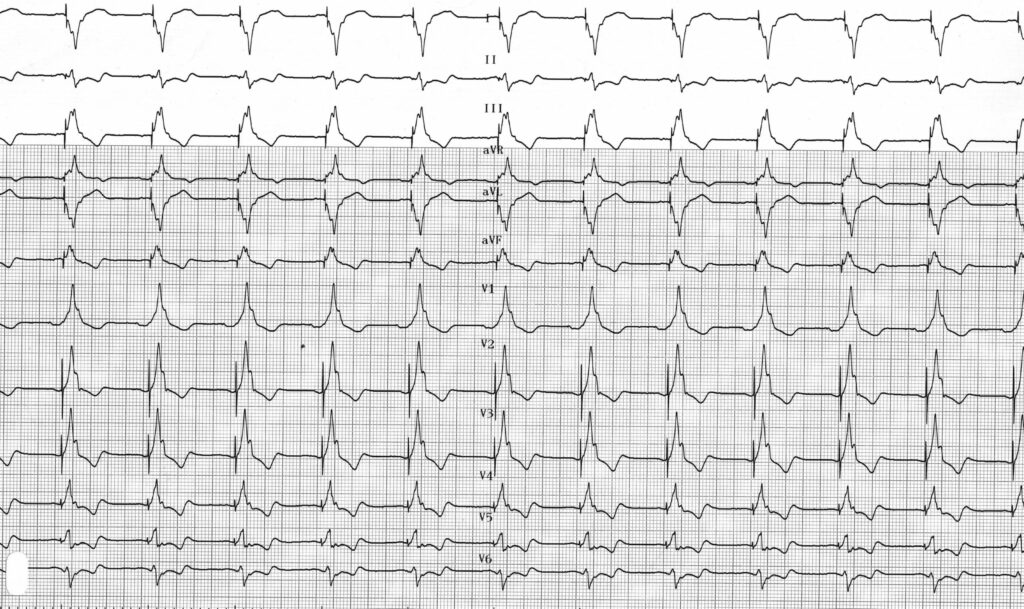

L’EGM confirme l’absence de capture ventriculaire avec sur unbattement, échappement jonctionnel;

Tracé enregistré dans la continuité du premier; majoration du nombre de stimulations ventriculaires inefficaces;

Ces tracés mettent en évidence une perte de capture ventriculaire intermittente chez un patient implanté d’un stimulateur double chambre dans le cadre d’un bloc auriculo-ventriculaire complet et donc dépendant de son stimulateur. Une perte intermittente de capture par élévation du seuil de stimulation ventriculaire entraine la survenue de syncopes avec un risque élevé de mort subite.

Ce patient a bénéficié d’une augmentation de l’amplitude de stimulation (augmentation de 2.5 à 4 Volts pour un seuil à 2.6 V) ce qui a permis de supprimer les symptômes.

L’interrogation confirme l’élévation du seuil ventriculaire droit; ce tracé est enregistré après augmentation de l’amplitude de stimulation et montre une capture effective permanente;